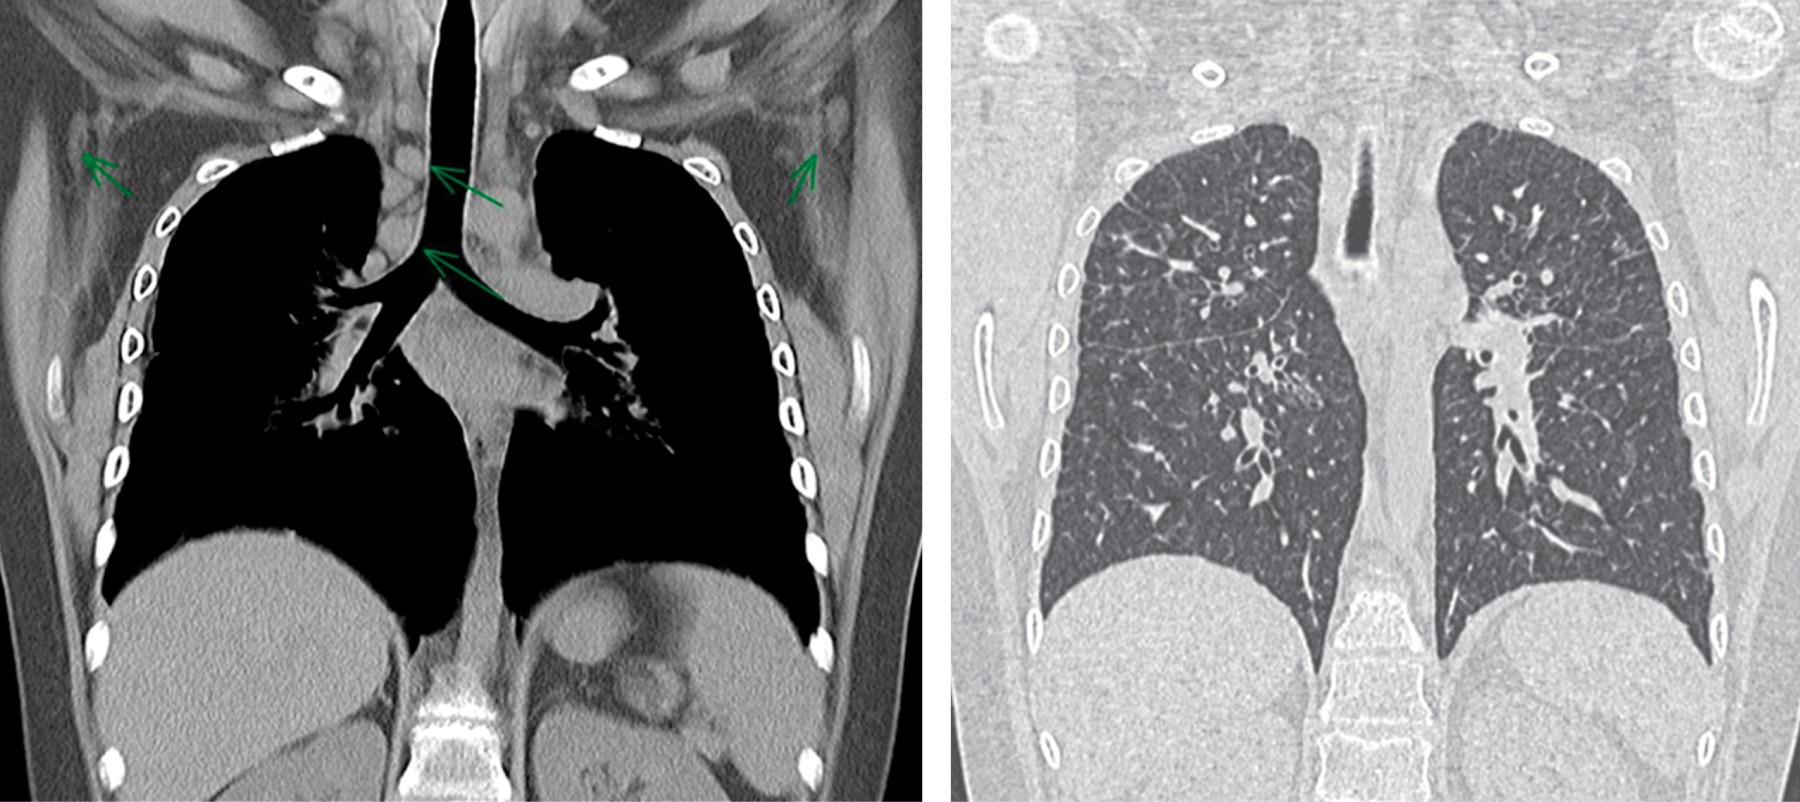

La radiografía de tórax inicial mostró: ensanchamiento parahiliar bilateral por crecimientos ganglionares y un patrón intersticial fino bilateral y difuso, casi simétrico con algunas imágenes micronodulares bilaterales (Figura 1).

La tomografía axial computarizada de alta resolución (TACAR) pulmonar inicial mostró un patrón retículo nodular fino difuso con engrosamiento bronquial discreto y crecimientos nodulares parahiliares bilaterales (Figura 2). La espirometría mostró un patrón restrictivo sin respuesta significativa al uso del broncodilatador.

Ante este deterioro acude nuevamente a nuestro servicio y recibe tratamiento con prednisona a 1 mg/kg/día y metotrexato a 15 mg/m2/semana y se suspende micofenolato de mofetilo; con este cambio, a los dos meses de tratamiento hubo mejoría de la uveítis, sin depósitos, ni queratopatía y presión intraocular normal, la sintomatología respiratoria desapareció y hubo evidente mejoría por radiografía de tórax y por TACAR con desaparición de los crecimientos ganglionares parahiliares, de las imágenes micronodulares y del patrón intersticial (Figura 7).

Nuestros casos se clasifican en el estadio II, ya que en la TACAR se detectó adenopatía hiliar bilateral con infiltrados pulmonares (Tabla 1).